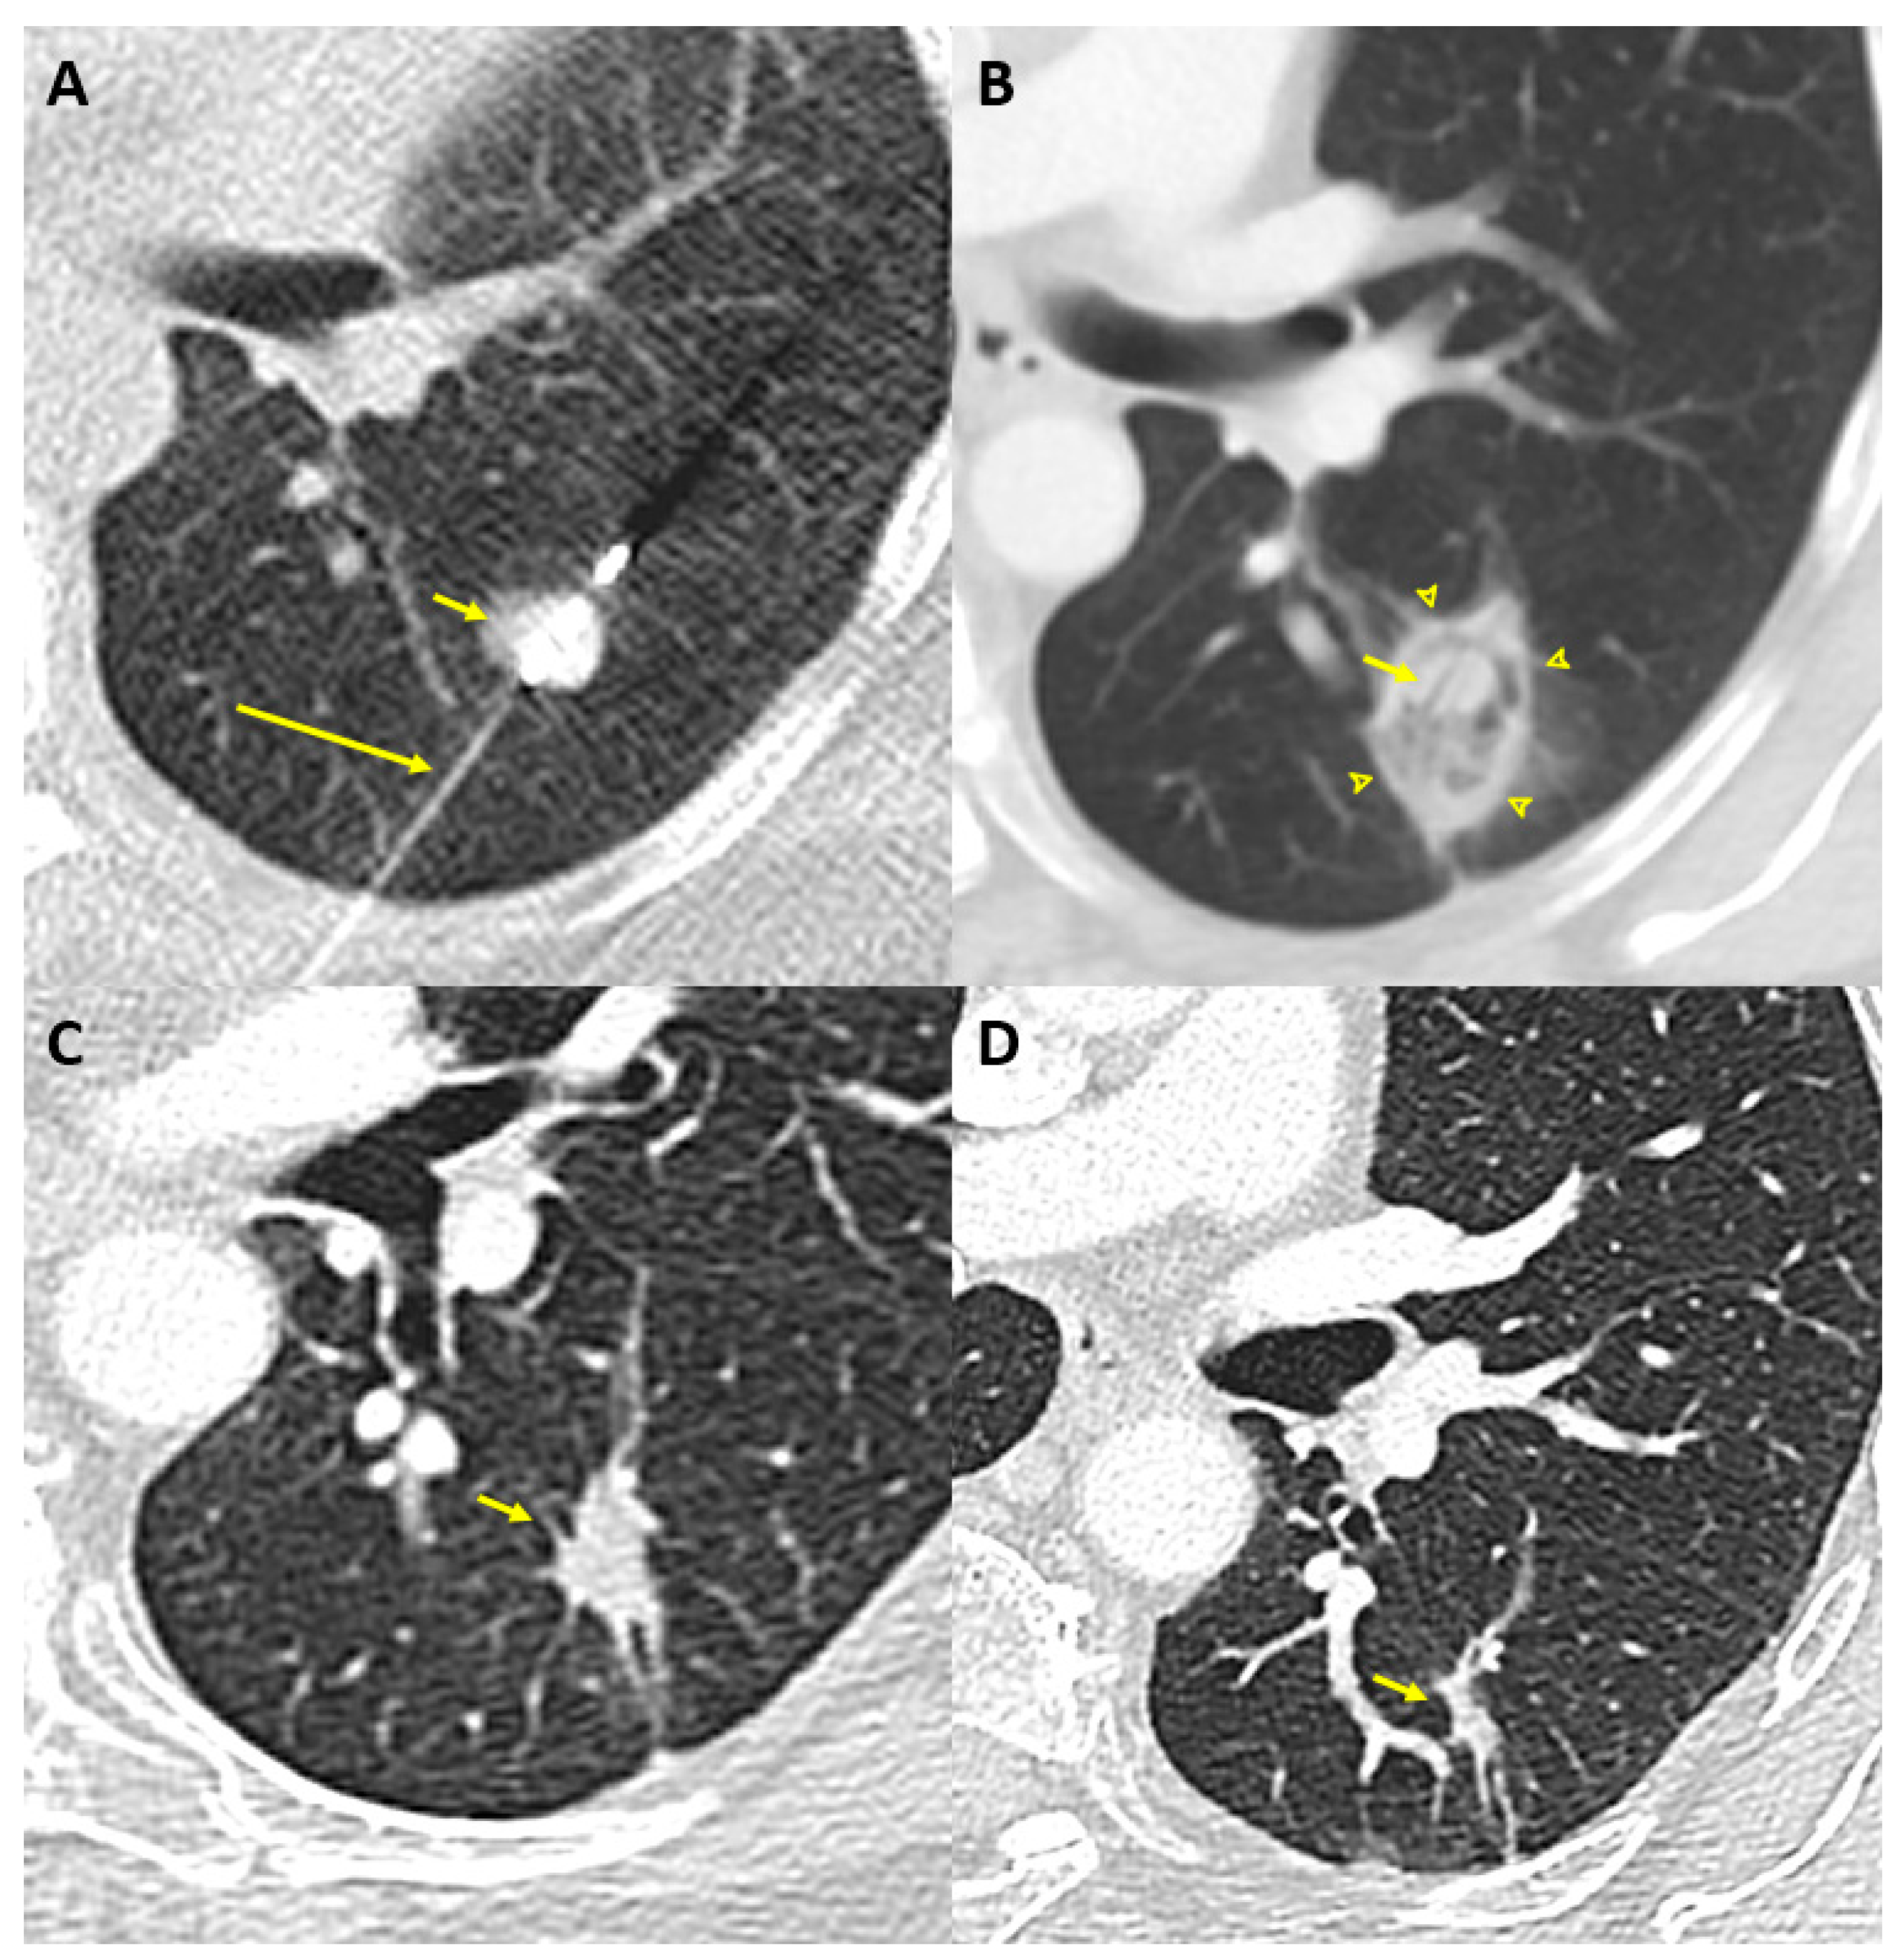

MWA uses oscillating electromagnetic waves (300 MHz to 300 GHz) emitted by the antenna to induce rapid flip motion of surrounding water molecules and increase local temperature [39]. Since it is less dependent on tissues properties, MWA reaches higher temperatures than RFA, and does so faster as well [40]. It also allows larger ablation zones by enabling simultaneous activation of multiple probes [41]. Given these advantages and its lower susceptibility to heat sink effect, MWA is increasingly being used for the treatment of lung and liver malignancies [42]. The main limitations of this technology are a lack of sphericity and only moderate reproducibility of the ablation zones [43]. An example of MWA in a sixty-year-old woman with a 13 mm nodule in the apical segment of the left lower lobe is shown in Figure 1.

Figure 1.

Example of MWA in a sixty-year-old woman with a 13 mm nodule in the apical segment of the left lower lobe. (A) Axial non-contrast chest computed tomography scan obtained during the MWA procedure shows the MWA probe (long arrow) placed percutaneously in the nodule (short arrow). (B) The computed tomography scan performed 6 weeks post-ablation shows a ground glass opacity (arrowheads) surrounding the nodule (short arrow) and corresponding to the ablation zone. In this case, technical success was confirmed with an ablation margin above 10mm. (C) Chest-computed tomography performed 13 months later confirmed the expected decrease in size post-ablation (short arrow). (D) Sixty-one months later, the post-ablation zone markedly decreased in size (short arrow), with no signs of local recurrence.